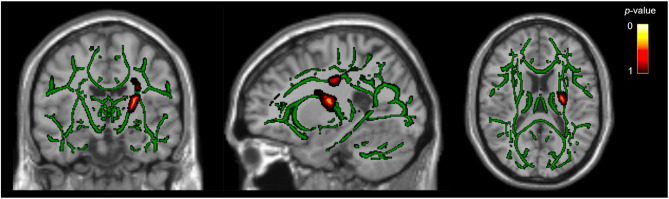

White matter tract differences in persistent post-traumatic headache, migraine, and healthy controls: a diffusion tensor imaging study.